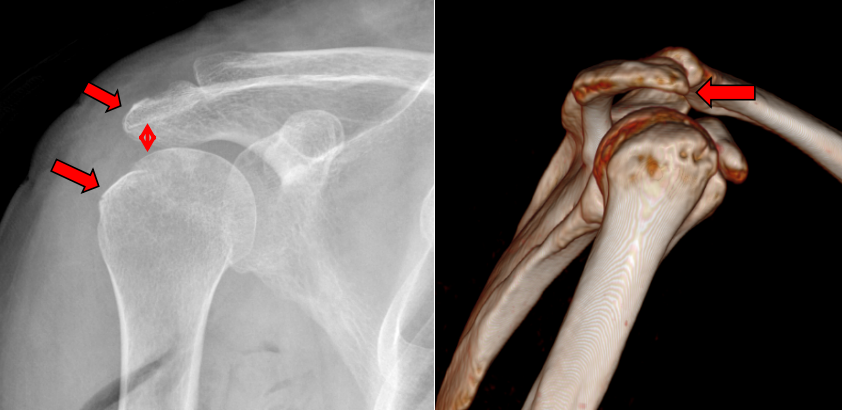

王某某,女,61岁,3个月前因摔伤致右肩部肿痛伴功能受限,于当地医院住院1周后因右肩部疼痛加重伴活动受限来我院就诊。行右肩MRI检查示:右肱骨大结节骨折,伴冈上肌腱部分撕裂、肩胛下肌腱损伤、肱二头长头肌腱炎、关节囊粘连。